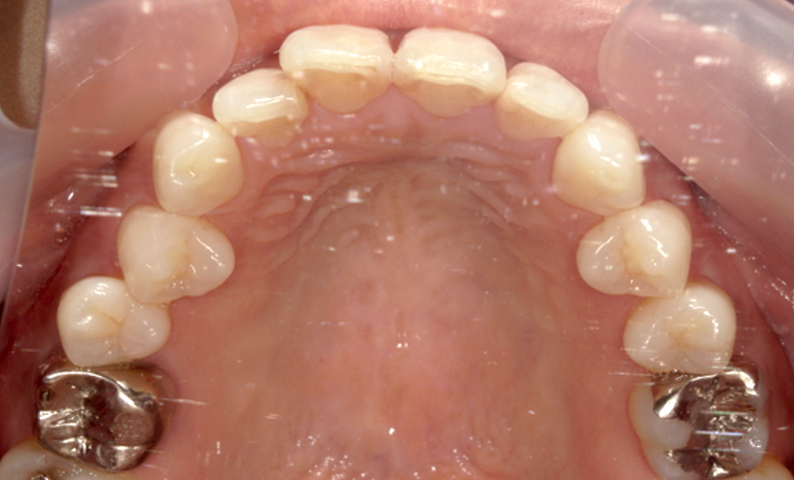

症例_001 前歯「捻転歯」症例

治療期間:6ヶ月金額:48万円+税20代女性少しのねじれ捻転歯下の八重歯

| Before | After |